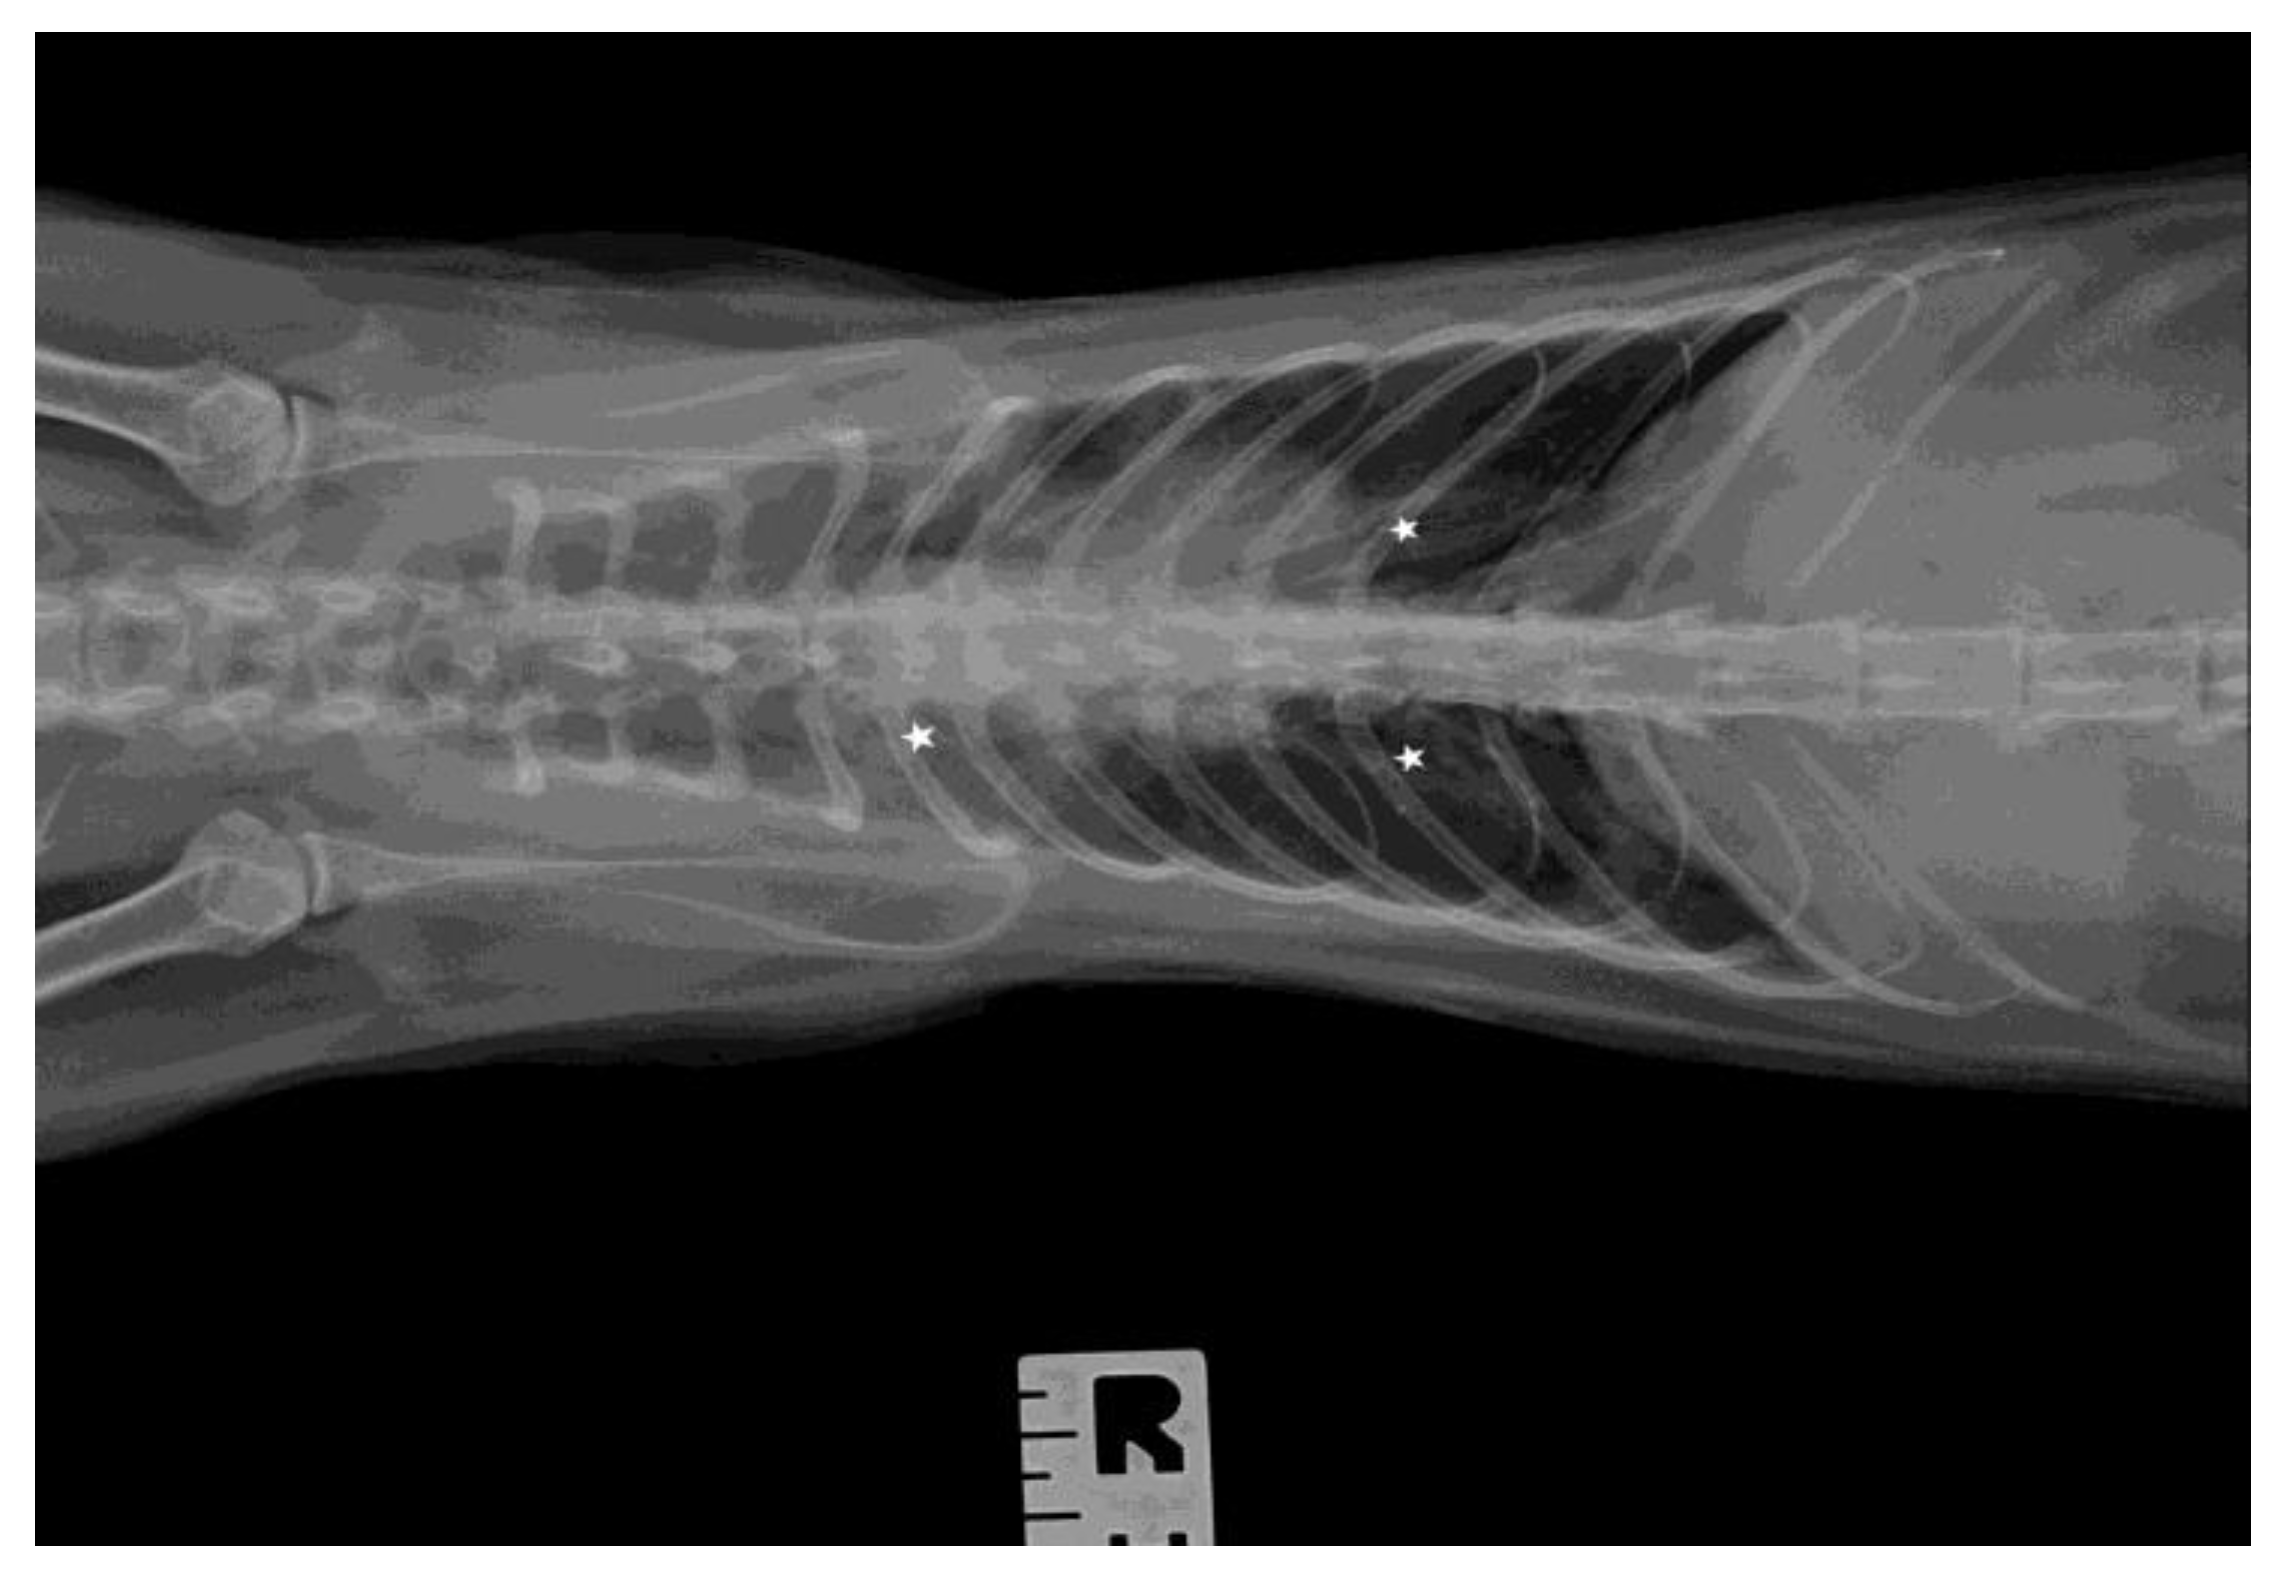

3.3. Ultrasound Examination and X-ray